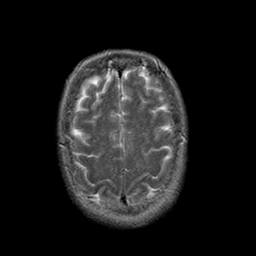

Stroke:T2-weighted MR #1 -- Slice #20

[Home][Help][Clinical] Slice 20